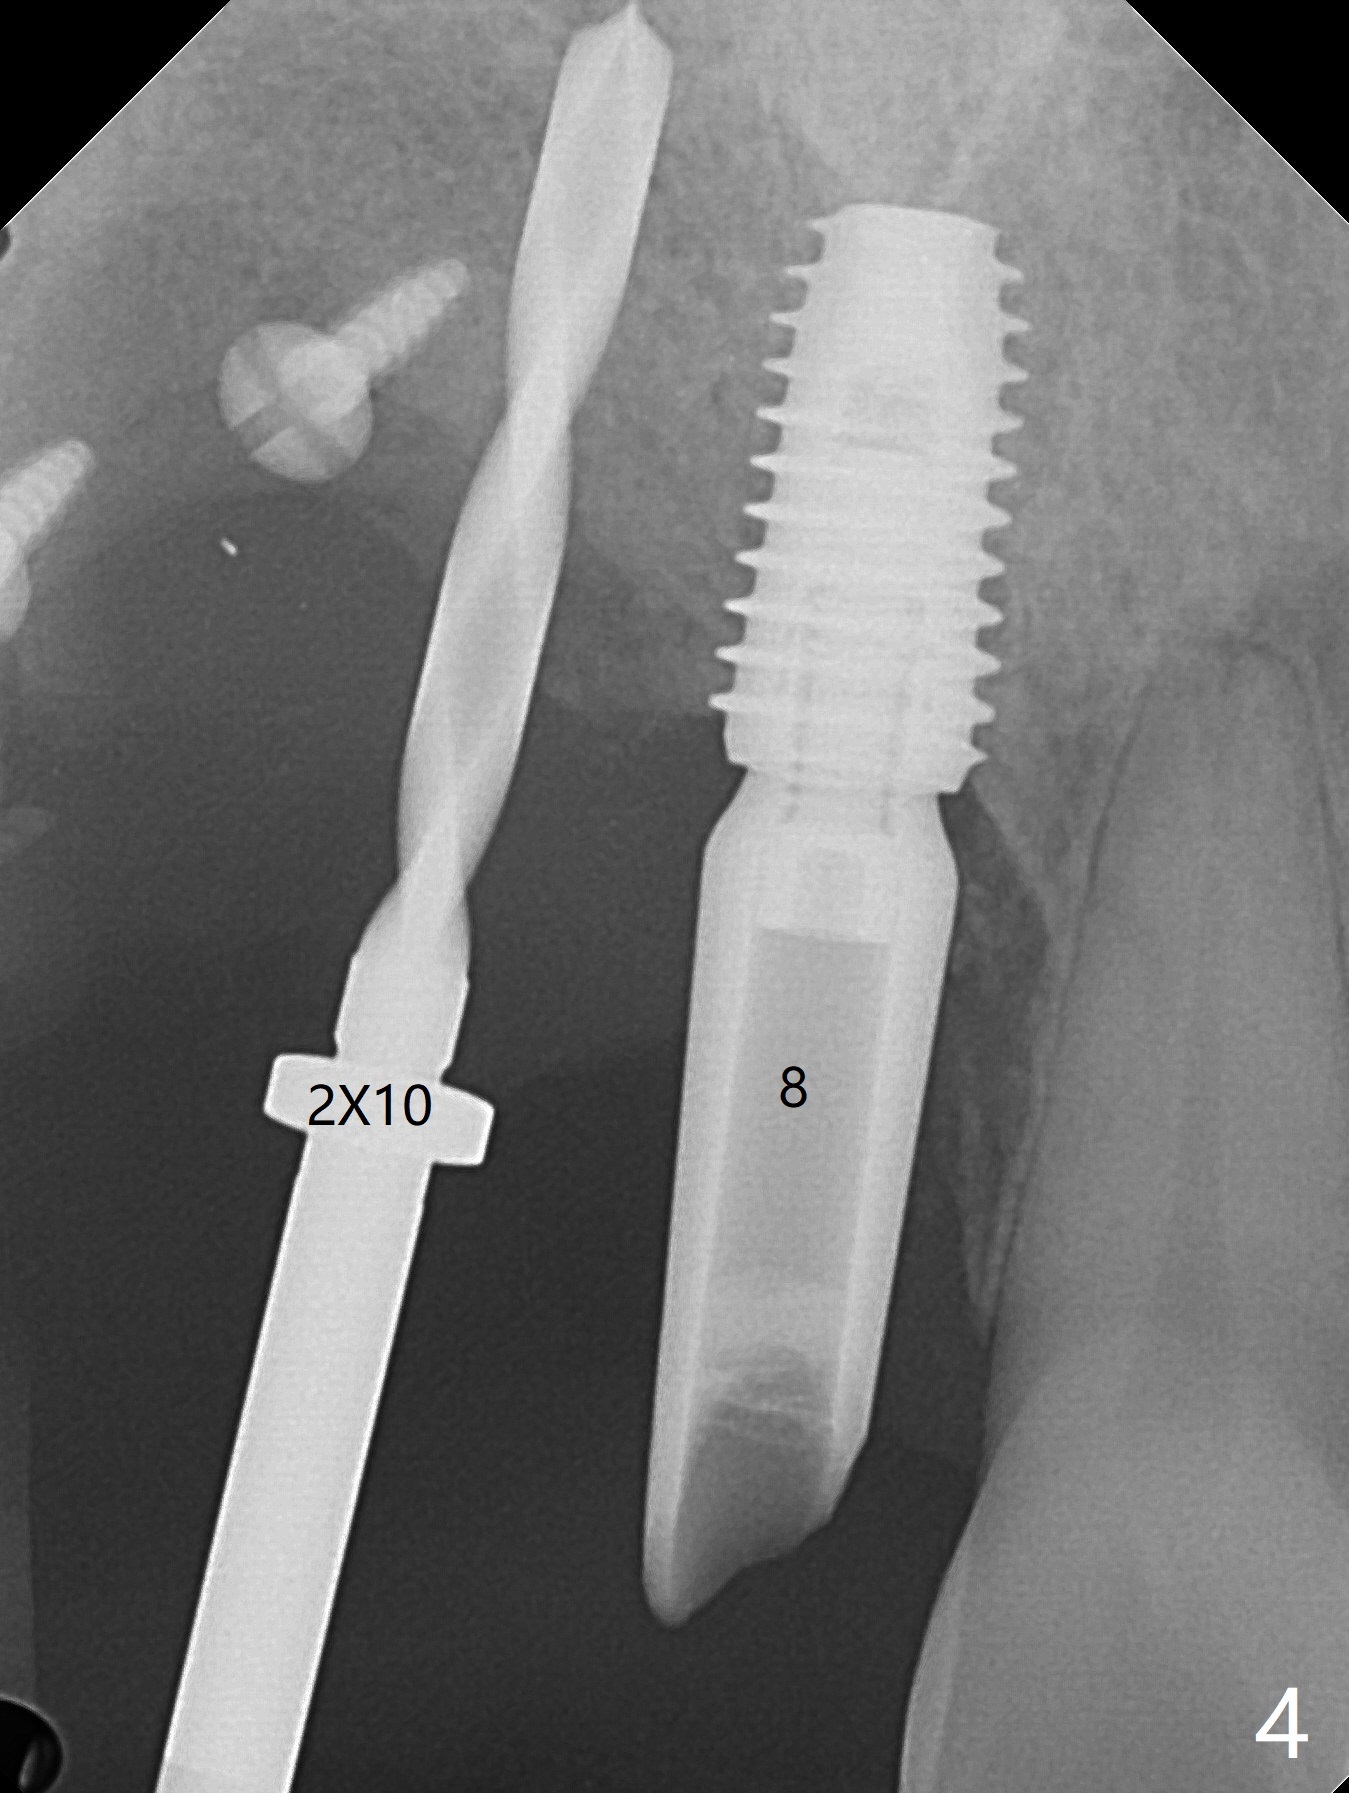

在6,7号牙位牙槽嵴切口,翻瓣,找不到上次放置的tenting screw,不过7号牙位骨质虽然低,够宽的,开始钻洞(图四),植入3.8乘8.5毫米植体,扭力足够(图五),近中舌侧暴露螺纹堆加骨粉(图五*),然后放置基台,再次在后者周围放置骨粉(图五至七),覆盖两张PRF膜后缝合(图八),最后在三个箭头周围放置牙周敷料。术后CT显示植体与tenting screws(图九,十箭头)有一定距离,但是5号牙植体颊侧根尖穿孔(图九 *)。如果植体不脱落,需做侧方切口植骨。术后七天7号植体腭侧肿胀(图十一 *),切开没有脓水,插入牙胶尖,它末端指向7号植体周围tenting screw。后者可能需要拔除,同时5号牙颊侧根尖植骨,但是为时太早,可能打搅骨粉生长。术后两周腭侧肿胀没有消失,但是不痛,继续观察。术后接近6个月,软组织正常(图十三),但是5,7植体周围没有骨质(图十四,五)。由于近中tenting screws周围软组织触痛(局麻不全情况下),螺钉取出(图十六,七(*)),而远中螺钉好像有帮助5植体螺纹骨粉撑起,所以留下(腭侧穿孔部分去除),最后放置粘性骨粉(图十八:*)和PRF膜(两张由7基台打孔固定)。